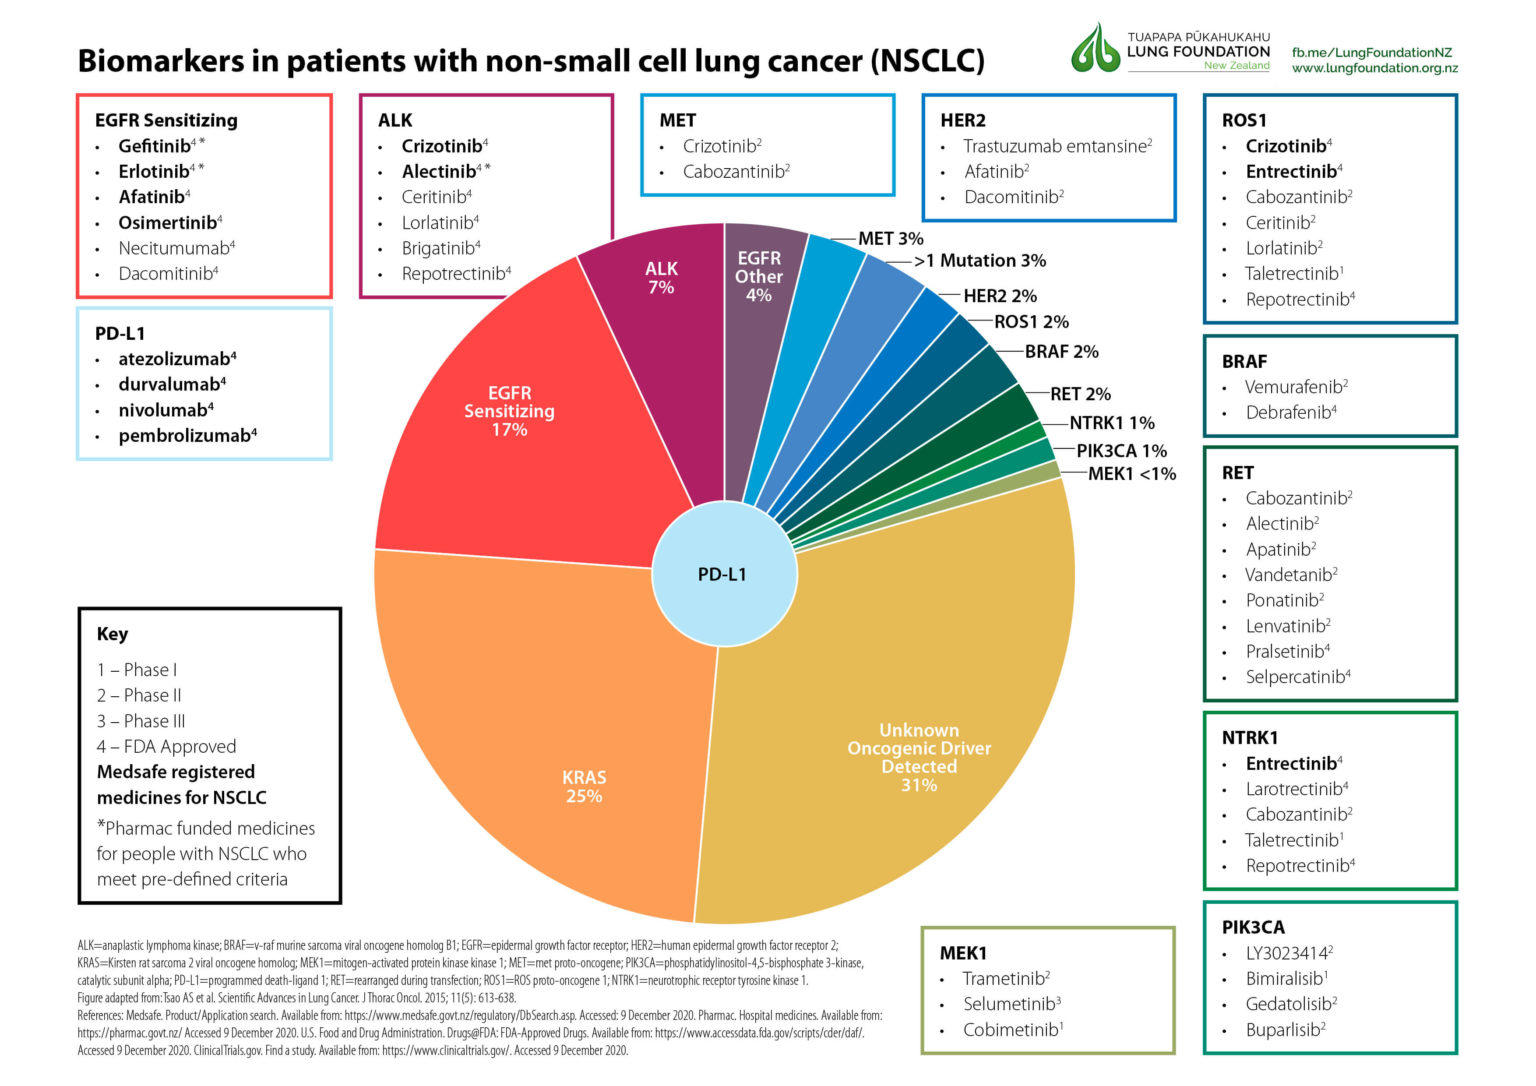

Our dataset of 416 patients and over 1.6 million cells provided sufficient power to make predictions using artificial intelligence. Depending on the type of cancer and the stage, you may receive a. Reducing or eliminating exposure to radon.